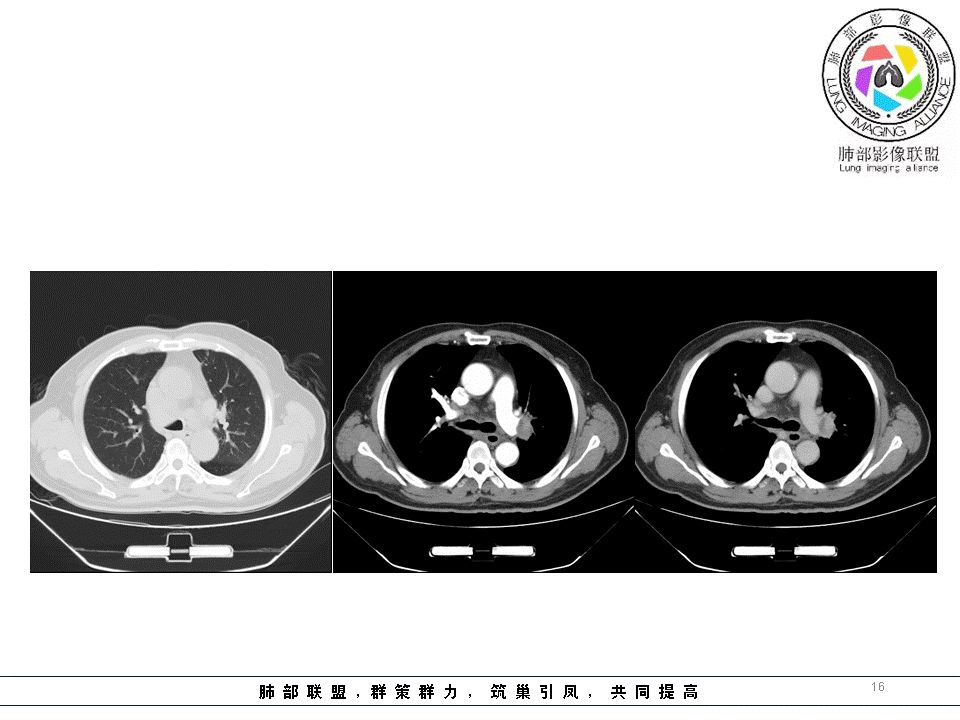

结果:肺腺癌并纵膈淋巴结转移

编后的话:

1.临床实践中我们可能会有过多次这样的经验,右锁骨上淋巴结病理肺腺癌,但未能明确原发病灶之所在。该例也是如此,也许在肺叶中瞒天过海,也许隐匿肺门结构间。

2.鳞癌转移迟,左侧支气管腔内阴影多次取材应当能够排除发生于腔内的鳞癌。况患者未引发阻塞性改变。

3.肺癌淋巴结转移多有一定规律可循。右肺病灶均沿右肺血管束、右肺门、右侧纵隔上行;左肺下叶病灶沿左下肺血管束、左肺门、隆凸及右侧纵隔上行;左肺上叶病灶沿左上肺血管束、左肺门、主动脉窗及左侧纵隔上行。

该例左肺门及腔静脉后淋巴结肿大,是符合这规律的。

4.结节病偏偏双肺门淋巴结增大为主要特点,淋巴结密实且密度偏高。

5.淋巴瘤则主要位于前上纵膈,多发,密度较均匀一致,大小相仿,且无左右之分。